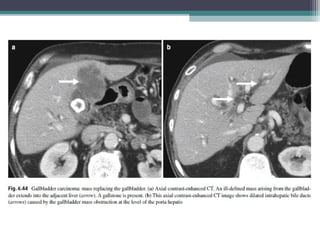

• CT :Typical finding include three patterns:

• 1)a mass replacing the gallbladder fossa (most common)

• 2)an intraluminal polypoid mass

• 3)gallbladder wall thickening.

• The mass fills most of the enlarged and deformed gallbladder, obscuring the

peripheral enhancement in the early phase and progressive enhancement in the

GALLBLADDER CARCINOMA • Adenocarcinomais the most common histologic type, accounting for 85% to 90% of cases. Other types are squamous or adenosquamous cell carcinoma   • The risk factors : Gallstones, congenital abnormal pancreaticobiliary ductal union, porcelain gallbladder , Chronic cholecystitis , Chronic typhoid infection and UC   • MODE OF SPREAD • a)Direct extension into adjacent structures such as the liver, hepatoduodenal ligament, colon, and duodenum . The liver is the most common site of invasion because of its proximity and the lack of serosa in the gallbladder wall where it is adjacent to the liver. • b)Lymphatic spread to regional and distant lymph nodes is also common in gallbladder carcinoma. •

• Foramen ofWinslow lymph node and the superior pancreaticoduodenal node are the most frequent sites of nodal metastases • The other pathways of tumor spread c)Hematogenous metastasis to the liver, • d) intraductal tumor spread e) peritoneal seeding . • Biliary obstruction can be in present gallbladder carcinoma, because of direct invasion of the bile duct in the porta hepatis, to metastatic lymphadenopathy, or to intraductal spread of tumor . • IMAGING : • CT :Typical finding include three patterns: • 1)a mass replacing the gallbladder fossa (most common) • 2)an intraluminal polypoid mass • 3)gallbladder wall thickening. • The mass fills most of the enlarged and deformed gallbladder, obscuring the peripheral enhancement in the early phase and progressive enhancement in the late phase.

• 103.

• This typeof gallbladder carcinoma often invades adjacent structures, including the liver . • An intraluminal polypoid mass is less common; differentiation ofpolypoid gb carcinoma from benign polyps is based on size, with polypoid gallbladder carcinoma typically larger than 1 cm . • Most benign polyps, such as cholesterol polyps, and adenomas are small, measuring less than 1 cm. • The gallbladder wall thickening type of carcinoma may be difficult to distinguish from adenomyomatosis and cholecystitis (especially chronic cholecystitis and xanthogranulomatous cholecystitis) • MRI : • GB Ca usually have increased signal intensity and poorly delineated contours on T2- weighted images and either isointense or hypointense signal on T1-weighted images compared with the liver. • DWI : High b value DWI MRI helps in differenciating Benign from malignant lesions . Malignant lesions shows Higher signal than benign lesions at b value of 1000 s/mm2